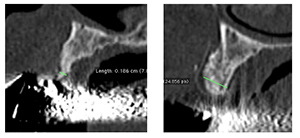

インプラント臨床において、GBR 法を併用することは必要不可欠であり、様々な補填材が市販されている。良好な結果を得ようとすれば、補填材と血液生体材料を併用することが必要であり、造成部に時間経過とともにどの程度の骨質を持った新生骨が作られるのかを予測することも必要である。骨の新生の度合いは個人によって大きな差があり、局所の状態によっても違う。今回の講義では、手術所見と組織像を対比し、術後の X 線像とも比較しながら、主に補填材としての Bio-Oss の用い方と勘所について症例を供覧したい。

3.BioOss, BioGide を使用した GBR